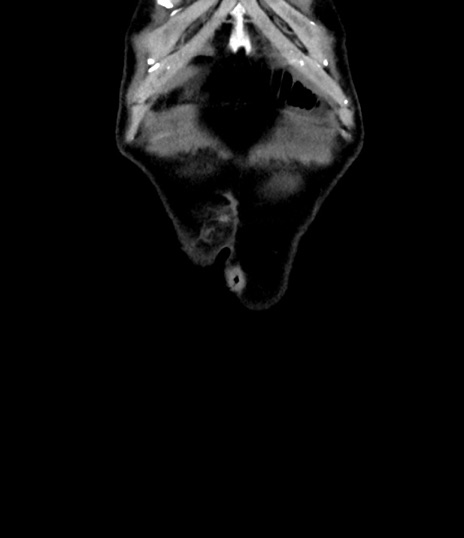

症例8(冠状断像)

【症例】 60歳代男性

【主訴】 黒色吐物

【現病歴】 4日前から嘔気自覚、2日前の朝食後にも嘔気あり、自分で手で嘔吐反射起こし嘔吐したところ血が混ざっていたため受診。

【既往歴】 5年前汎発性腹膜炎を伴う急性虫垂炎で手術、高血圧、前立腺肥大症、高脂血症

【身体所見】 腹部正中に手術癩痕あり 腹部平坦・軟圧痛なし膨満感あり

【データ】WBC 8400、CRP 4.54